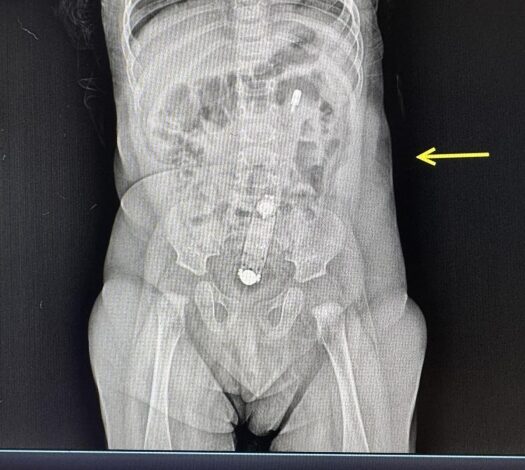

В Волынской области в больницу доставили маму с полугодовой девочкой, пострадавшей из-за использования электронного термометра вместо клизмы. По словам матери, она пыталась помочь ребенку с запором, воспользовавшись советом из интернета, что привело к опасной ситуации.

Термометр оказался полностью в кишечнике ребенка, что подтверждено рентгеном.

«Достать прибор было очень непросто. Это сделали эндоскопически. Действовать нужно осторожно, чтобы не травмировать анус и внутренние органы ребенка. Термометр самостоятельно выйти не мог, вместо этого мог перфорировать кишечник или вызвать непроходимость».